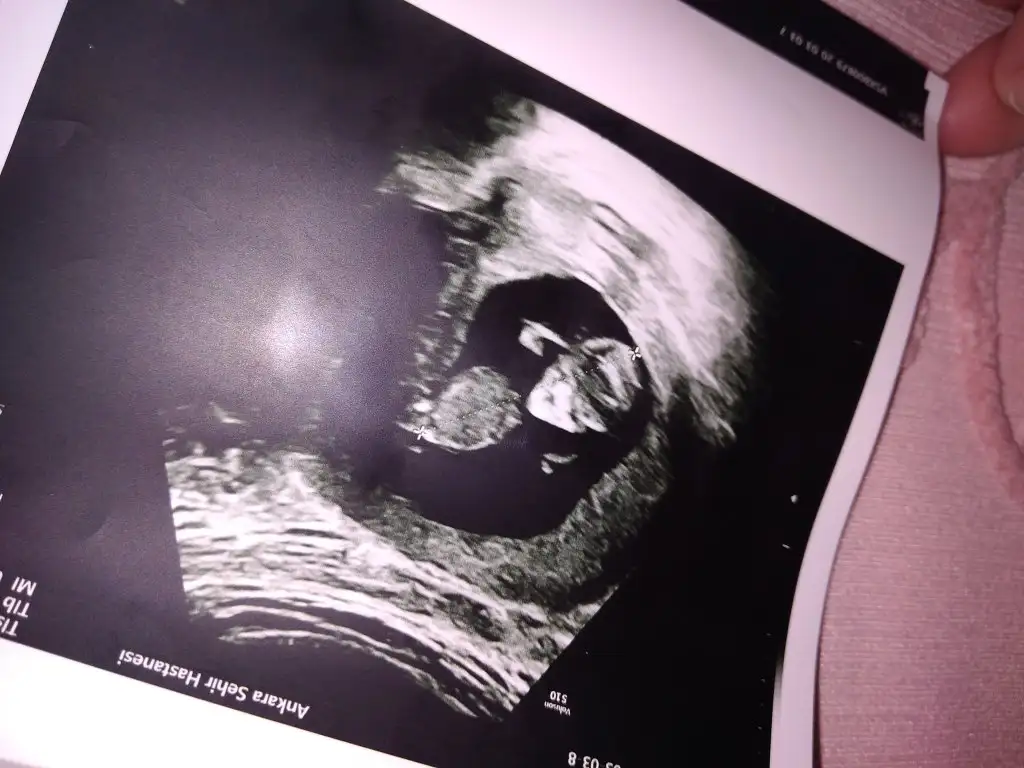

arkadaşımın yeni usg.. 15. hafta içinde ama doktor görememiş bacakları havaya dikmiş cinsiyetini görememiş.. tahmini olan var mı? gerçi artık nuba bakılamıyor sanırım bu haftalarda.. yine de var mıdır tahmininiz 😊

Daha öncede arkadaşın usg diye paylaşmıştımız aynı arkadaşmı benim tahminim neydi 😊